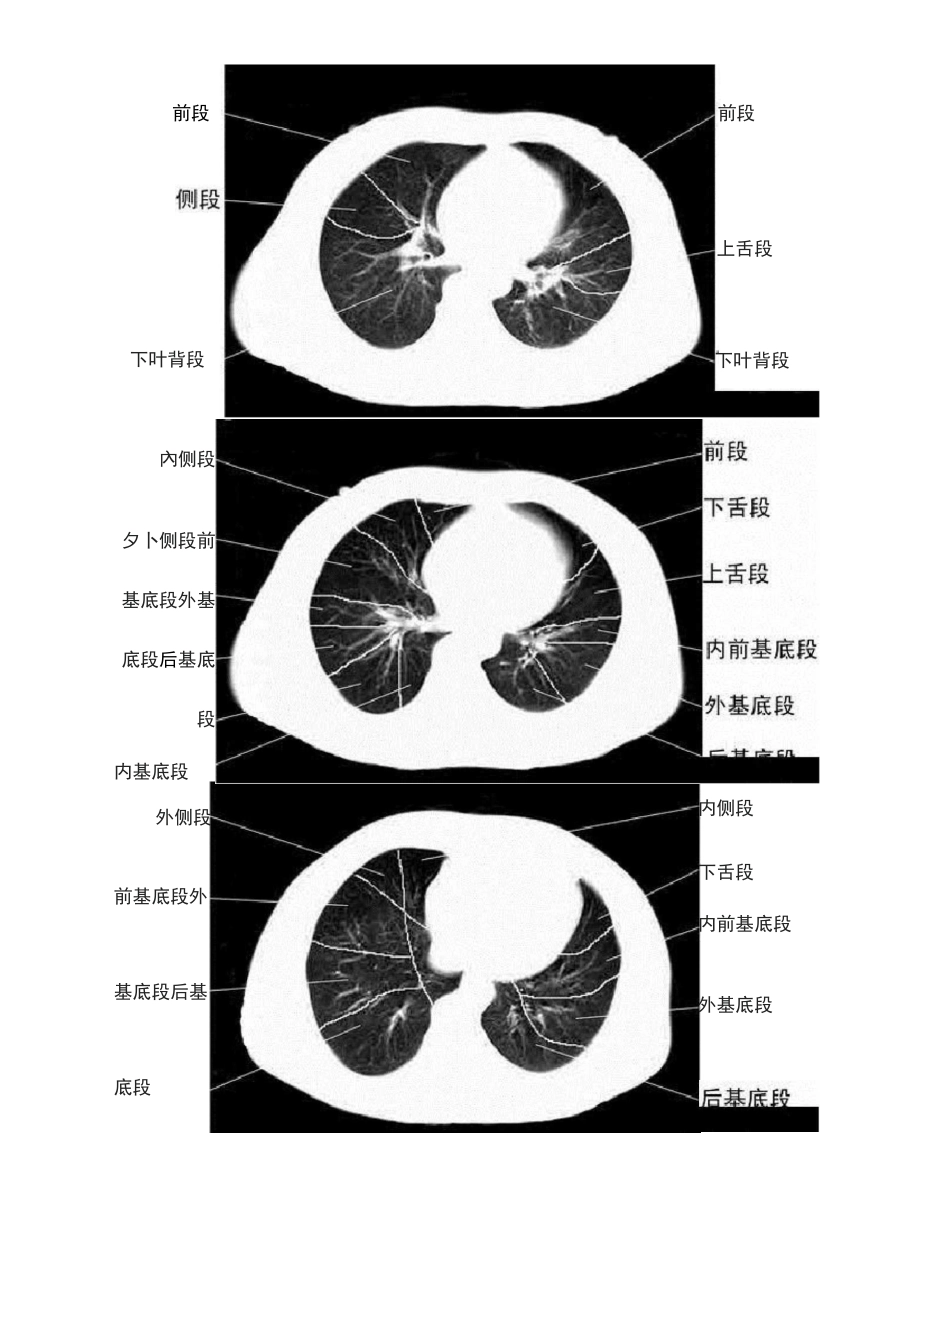

胸部 CT 肺段划分口诀独眼能看双上肺,左下还留一点背。对眼能看前后背,双眼能看前和背。嵴角出现能看中舌背,基底干出现就看余下肺。“独眼能看双上肺,左下还留一点背”:指气管层面,能显示两上肺,在偏下方层面,能看到左肺下叶背段“对眼能看前后背”:在支气管分叉层面(T4 以下)能看到两肺上叶前、后段及两肺下叶背段"双眼能看前和背":双眼与对眼都是指左右主支气管,“对眼”指左右主支气管距离近,"两眼"是气管分叉下方层面及肺动脉层面,左右支气管距离较远,此时断面图像上只能显示上叶前段和下叶背段"嵴角出现能看中舌背":嵴角指有中叶支气管与下叶支气管的夹角,内有右上肺静脉的断面,此层面能看到右肺中叶,左上肺舌叶及两肺下叶背段“基底干出现就看余下肺”:两下叶支气管分出基底段时能观察中叶,舌叶及两肺下叶各基底段,所以觉得此句应改为“基底干出现就看中舌余下肺”图解如下:前段i\xrn.尖后段后段前段前段尖段尖后段后段下叶背段下叶背段前段下叶昔段下叶背段內侧段夕卜侧段前基底段外基底段后基底段内基底段下叶背段下叶背段前段前段上舌段外侧段前基底段外基底段后基底段内侧段下舌段内前基底段外基底段右肺上叶右侧斜裂右肺下叶背段左肺上叶左侧斜裂左肺下叶背段右肺中叶右侧斜裂右肺下叶左肺上叶舌段左侧斜裂左肺下叶右肺上叶水平裂少血管带'右肺下叶左侧斜裂少血管带右肺上叶水平裂少血管带右侧斜裂右肺下叶左肺上叶左侧斜裂少血管带水平裂顶部右侧斜裂左主支气管右上叶尖段支气營右上叶支气管右上叶肺静脉后支左上叶尖后段支气管右主支气管 _ 左主支气管左肺动脉右主支气管支气營右下肺动脉干中间段支气管左肺上静脉左上叶舌毀支气管右肺中时动脉右中叶支气管右下肺动脉右下支气管咅下支气管左下肺动脉前内基底支左下肺动脉后外基底支左肺下静脉后右下叶内基底脱支气管右下肺动脉右下叶支气管右肺下静脉左肺下静脉左下肺内前基底段动脉左下叶内前基底駁支气管左下叶后基底